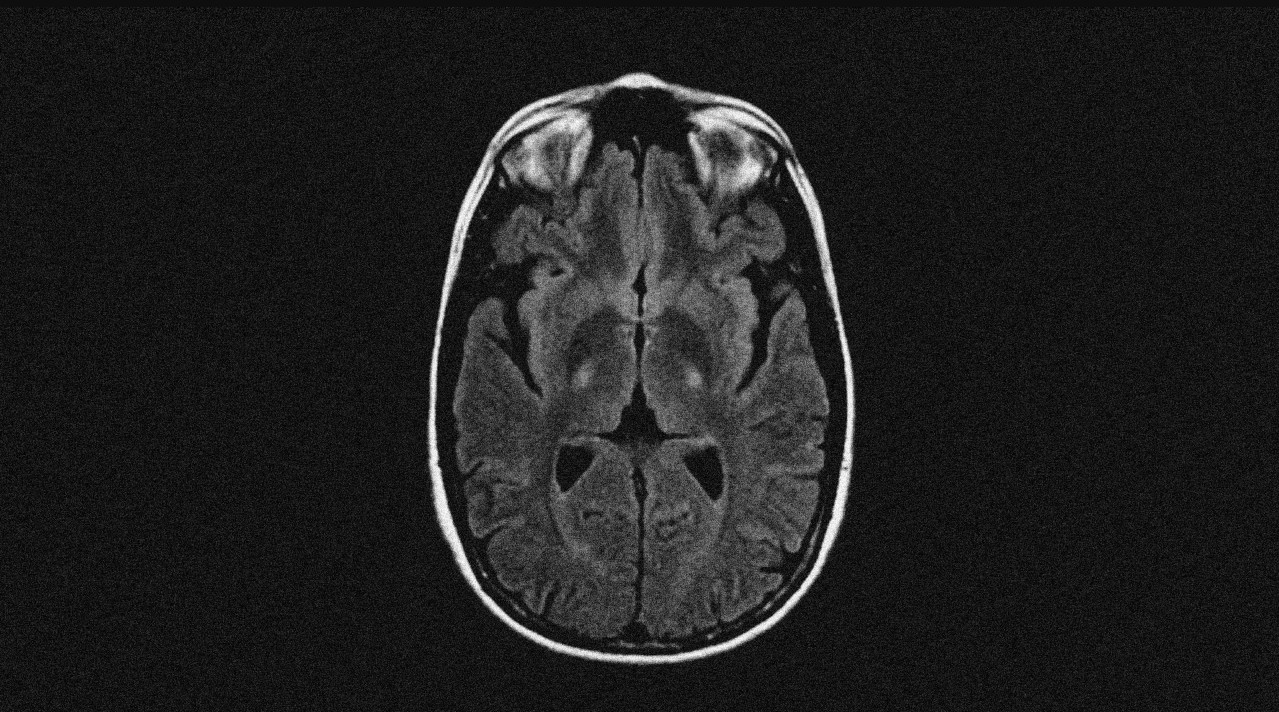

Через 35 лет тот же диагноз получил 80-летний диктатор. К тому времени версию о микробах-возбудителях всерьез уже не рассматривали, а нейродегенерацию считали одним из проявлений старения нервной системы. Было понятно, что в ткани мозга появляются какие-то бляшки — как при болезни Альцгеймера или Паркинсона — которые и вызывают прогрессирующий паралич. Именно эти бляшки, тогда еще неясной природы, за десять лет превратили бодрого старика, который и в 72 года переплывал Янцзы, — в безнадежного пациента, который мог дышать, только лежа на боку. От диагноза до смерти, как и в случае с бейсболистом, прошло около двух лет.

Британскому астрофизику повезло больше. Свой приговор он услышал еще до того, как его собрат по несчастью пересек Янцзы в последний раз, но болезнь остановилась в полушаге от летального финиша. Медленно теряя подвижность головы, ученый прожил еще 55 лет, стал иконой научпопа и новым символом своей болезни. За это время стало понятно, что агрегаты в мозге состоят из белков, у этих белков появились имена, а на горизонте замаячили возможные гены-виновники. Полсотни клинических испытаний лекарств стартовали и сошли с дистанции досрочно. Миллионы людей вылили на себя ведра ледяной воды, собирая деньги на исследование болезни. Но никто так и не понял, как ее лечить.

Боковой амиотрофический склероз (БАС), который погубил Лу Герига, Мао Цзэдуна и Стивена Хокинга — лишь одно из множества нейродегенеративных заболеваний, против которых человечество до сих пор бессильно. И хотя далеко не всегда БАС заканчивается деменцией, с болезнями Альцгеймера и Паркинсона его сравнивали не зря. Препятствия, которые отделяют нас от лекарства, во всех этих случаях примерно одни и те же: предсказать болезнь невозможно, диагностировать на ранних стадиях удается не всегда, причины многоообразны, а список их не полон.